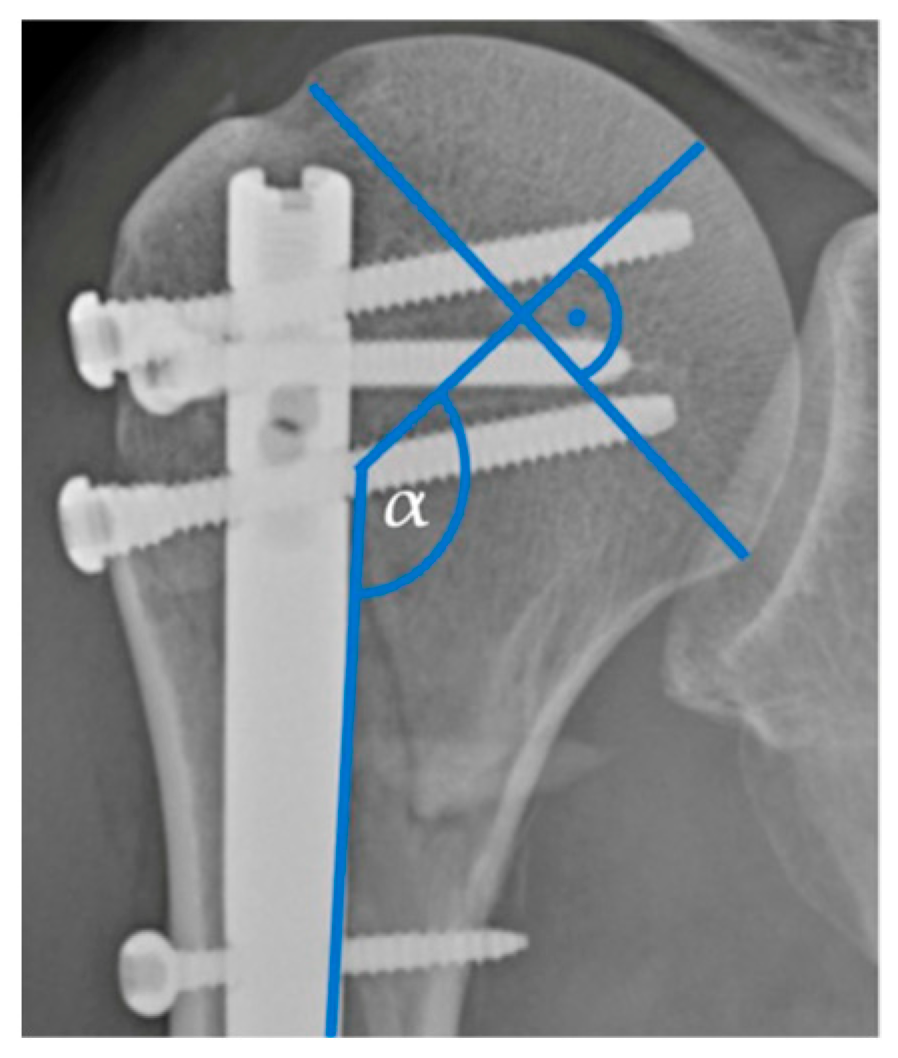

The pre- and postoperative radiographic imaging was assessed using Picture Archiving and Communication System software (Version: Ashvins 2017 Build 1637), which involved the analysis of plain radiographic images or computed tomography (CT) scans. Fractures were classified based on the number of fractured parts and according to the Neer classification system [16]. The analysis also focused on assessing the postoperative anatomical reposition of the fractures and the pre- and postoperative head–shaft angle (HSA) (Figure 1).

Figure 1. Head–shaft angle.